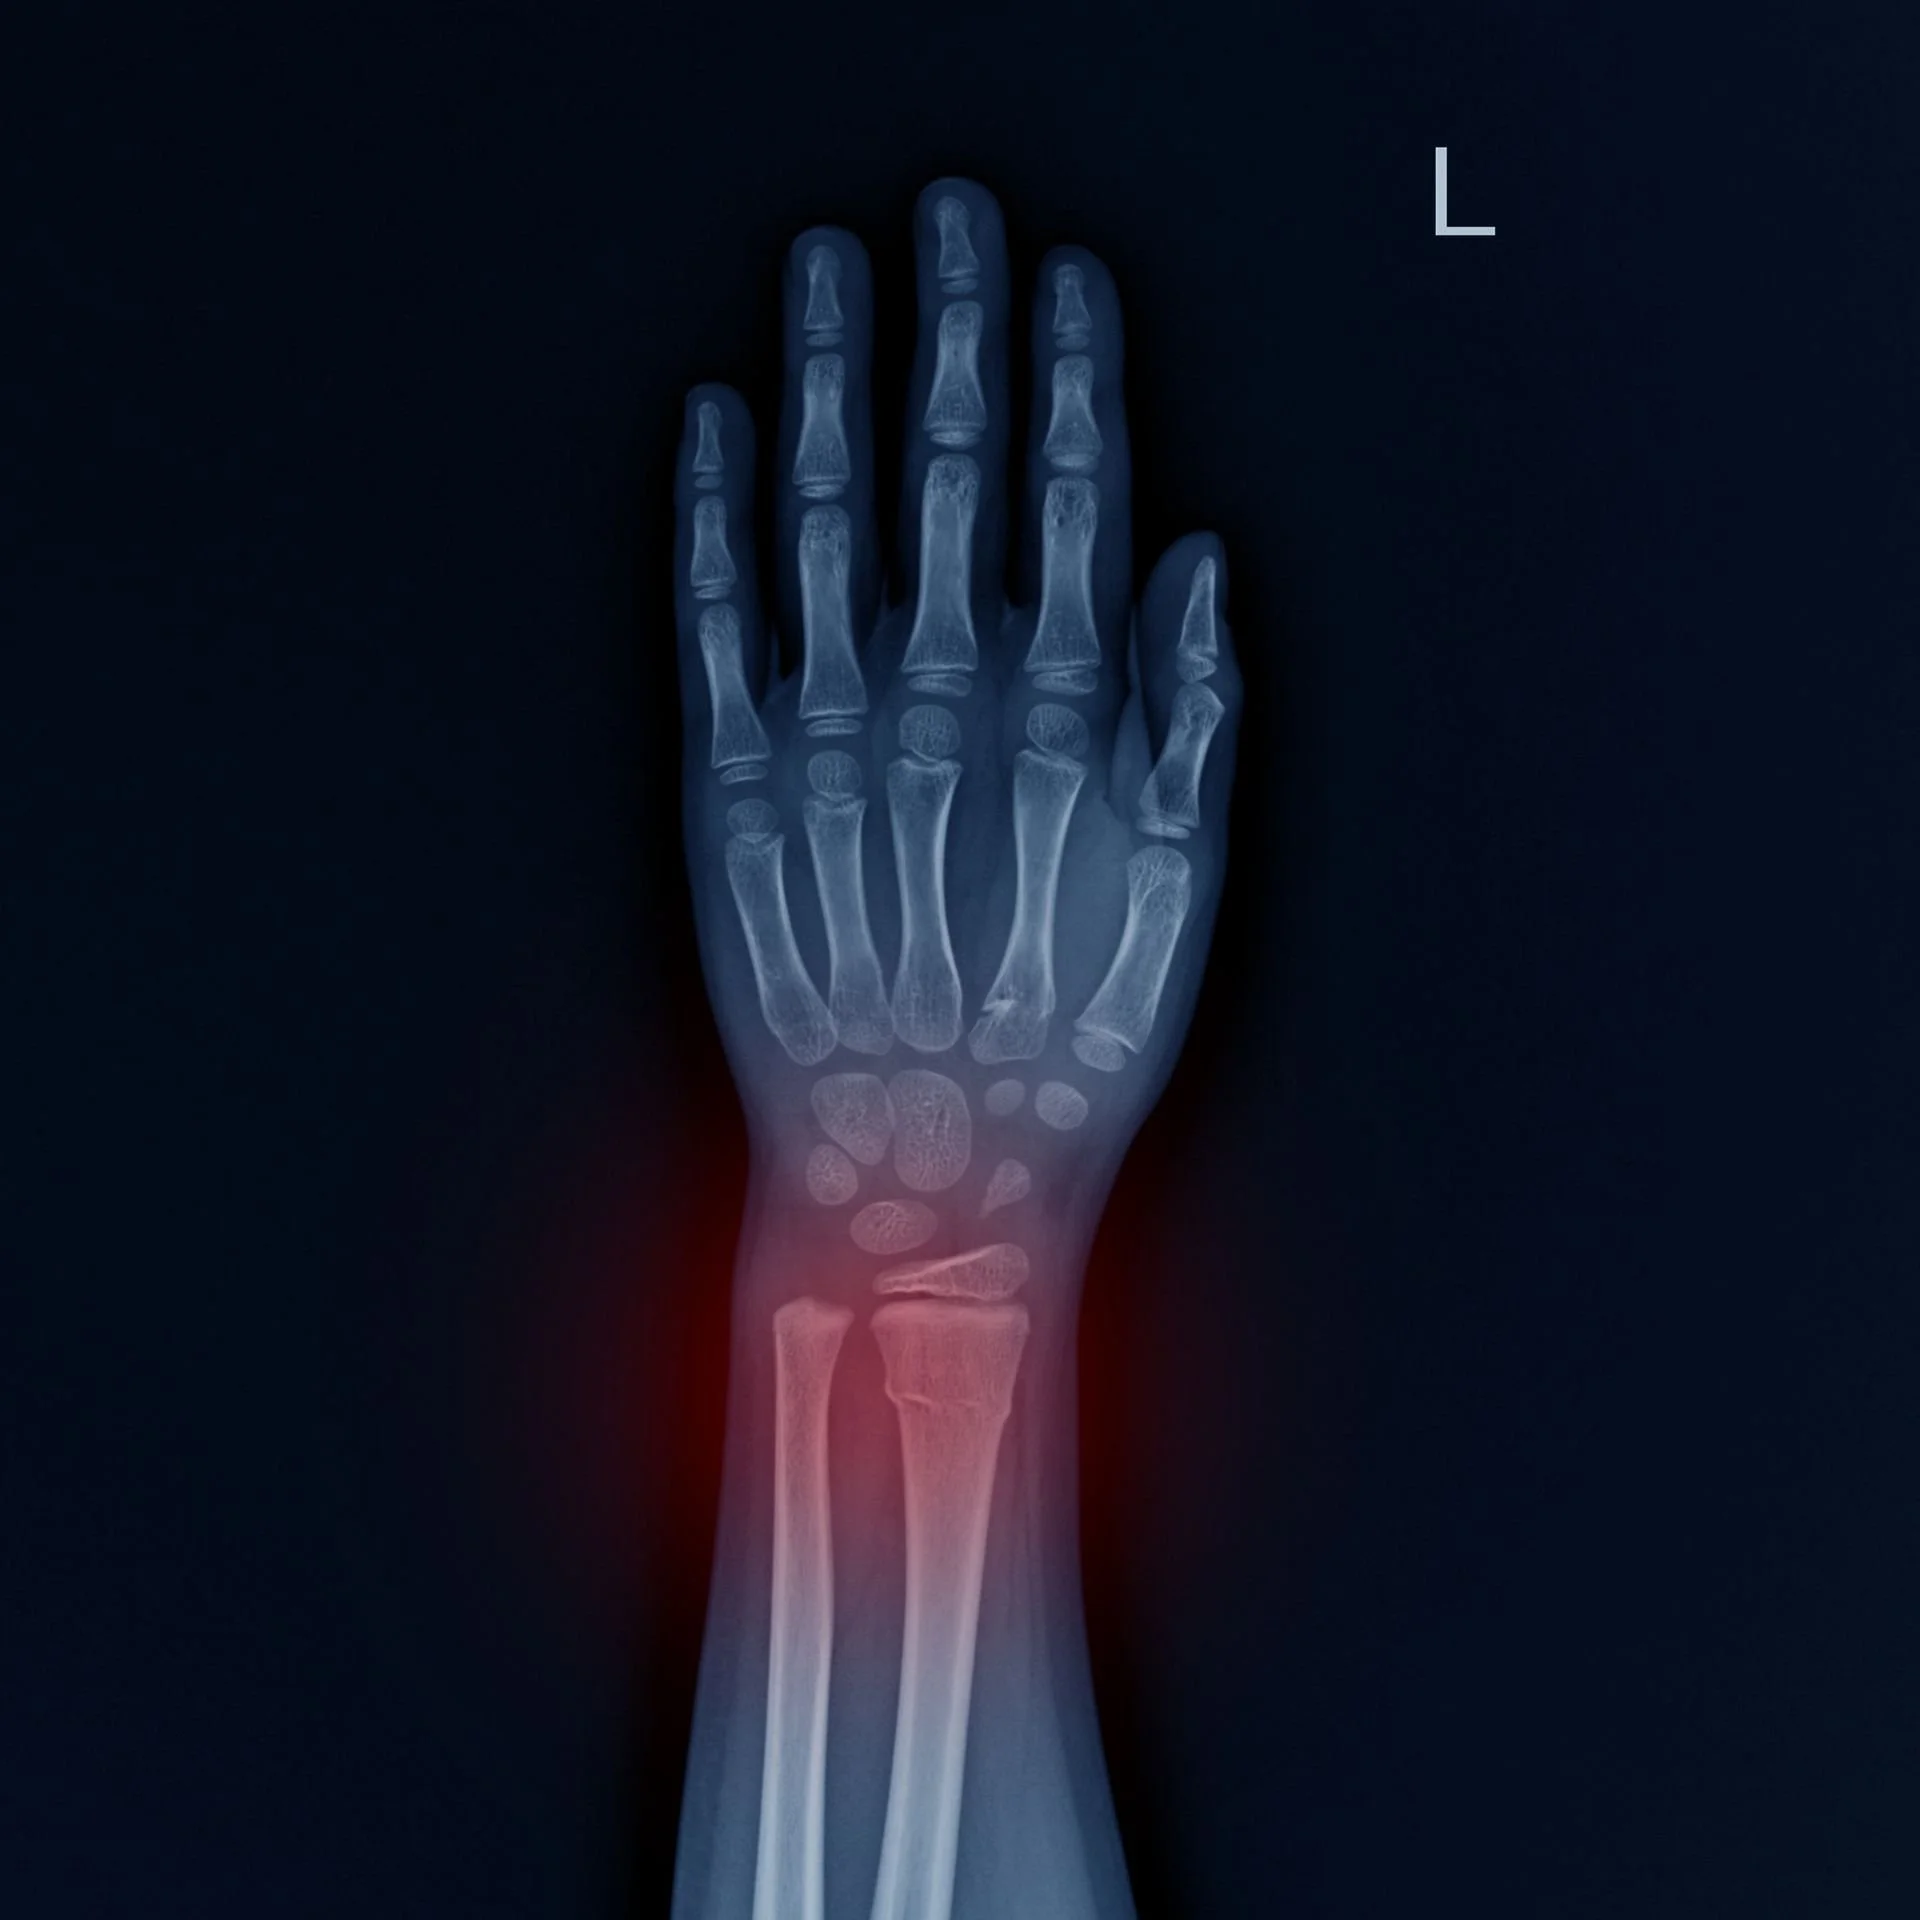

Fracture du poignet

La fracture du poignet, souvent une fracture de l’extrémité distale du radius (Pouteau‑Colles ou Goyrand‑Smith), résulte d’une chute sur la main ou d’un traumatisme direct. C’est l’une des fractures les plus fréquentes, particulièrement chez les personnes âgées ostéoporotiques et les jeunes sportifs.

Elle peut toucher le radius seul ou s’associer à une fracture de l’ulna et provoquer une déformation visible. Face à un tel traumatisme, une prise en charge rapide est essentielle pour éviter des complications et favoriser une bonne récupération.

Le diagnostic repose sur l’examen clinique et la réalisation de radiographies au moins dans deux incidences, face et profil.

En cas de suspicion de fracture complexe ou articulaire, un scanner peut être indiqué pour affiner la planification chirurgicale. Ces examens permettent de déterminer si la fracture est déplacée, instable ou associée à d’autres lésions (ligamentaires, scaphoïde…), et d’évaluer les risques potentiels d’arthrose ou de pseudarthrose.